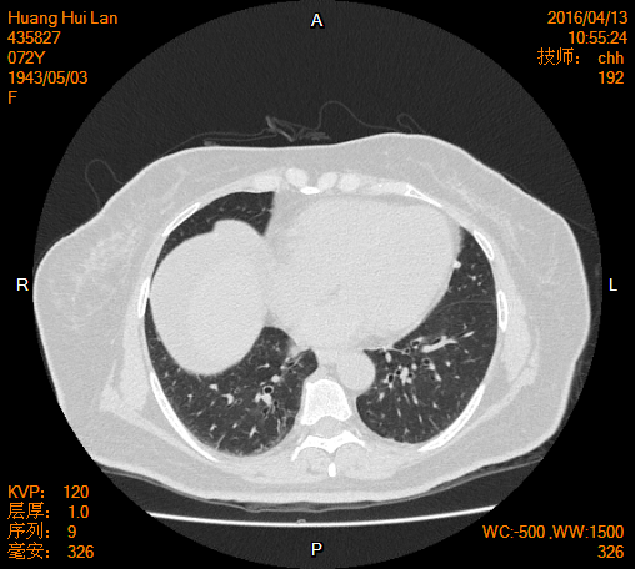

2016-04-13胸腹盆CT

左侧附件区肿块,代谢活跃,考虑卵巢囊腺癌;直肠壁增厚,代谢活跃,考虑直肠癌并周围淋巴结转移可能性大,建议肠镜检查;双肺多发结节,考虑转移瘤;腹腔积液